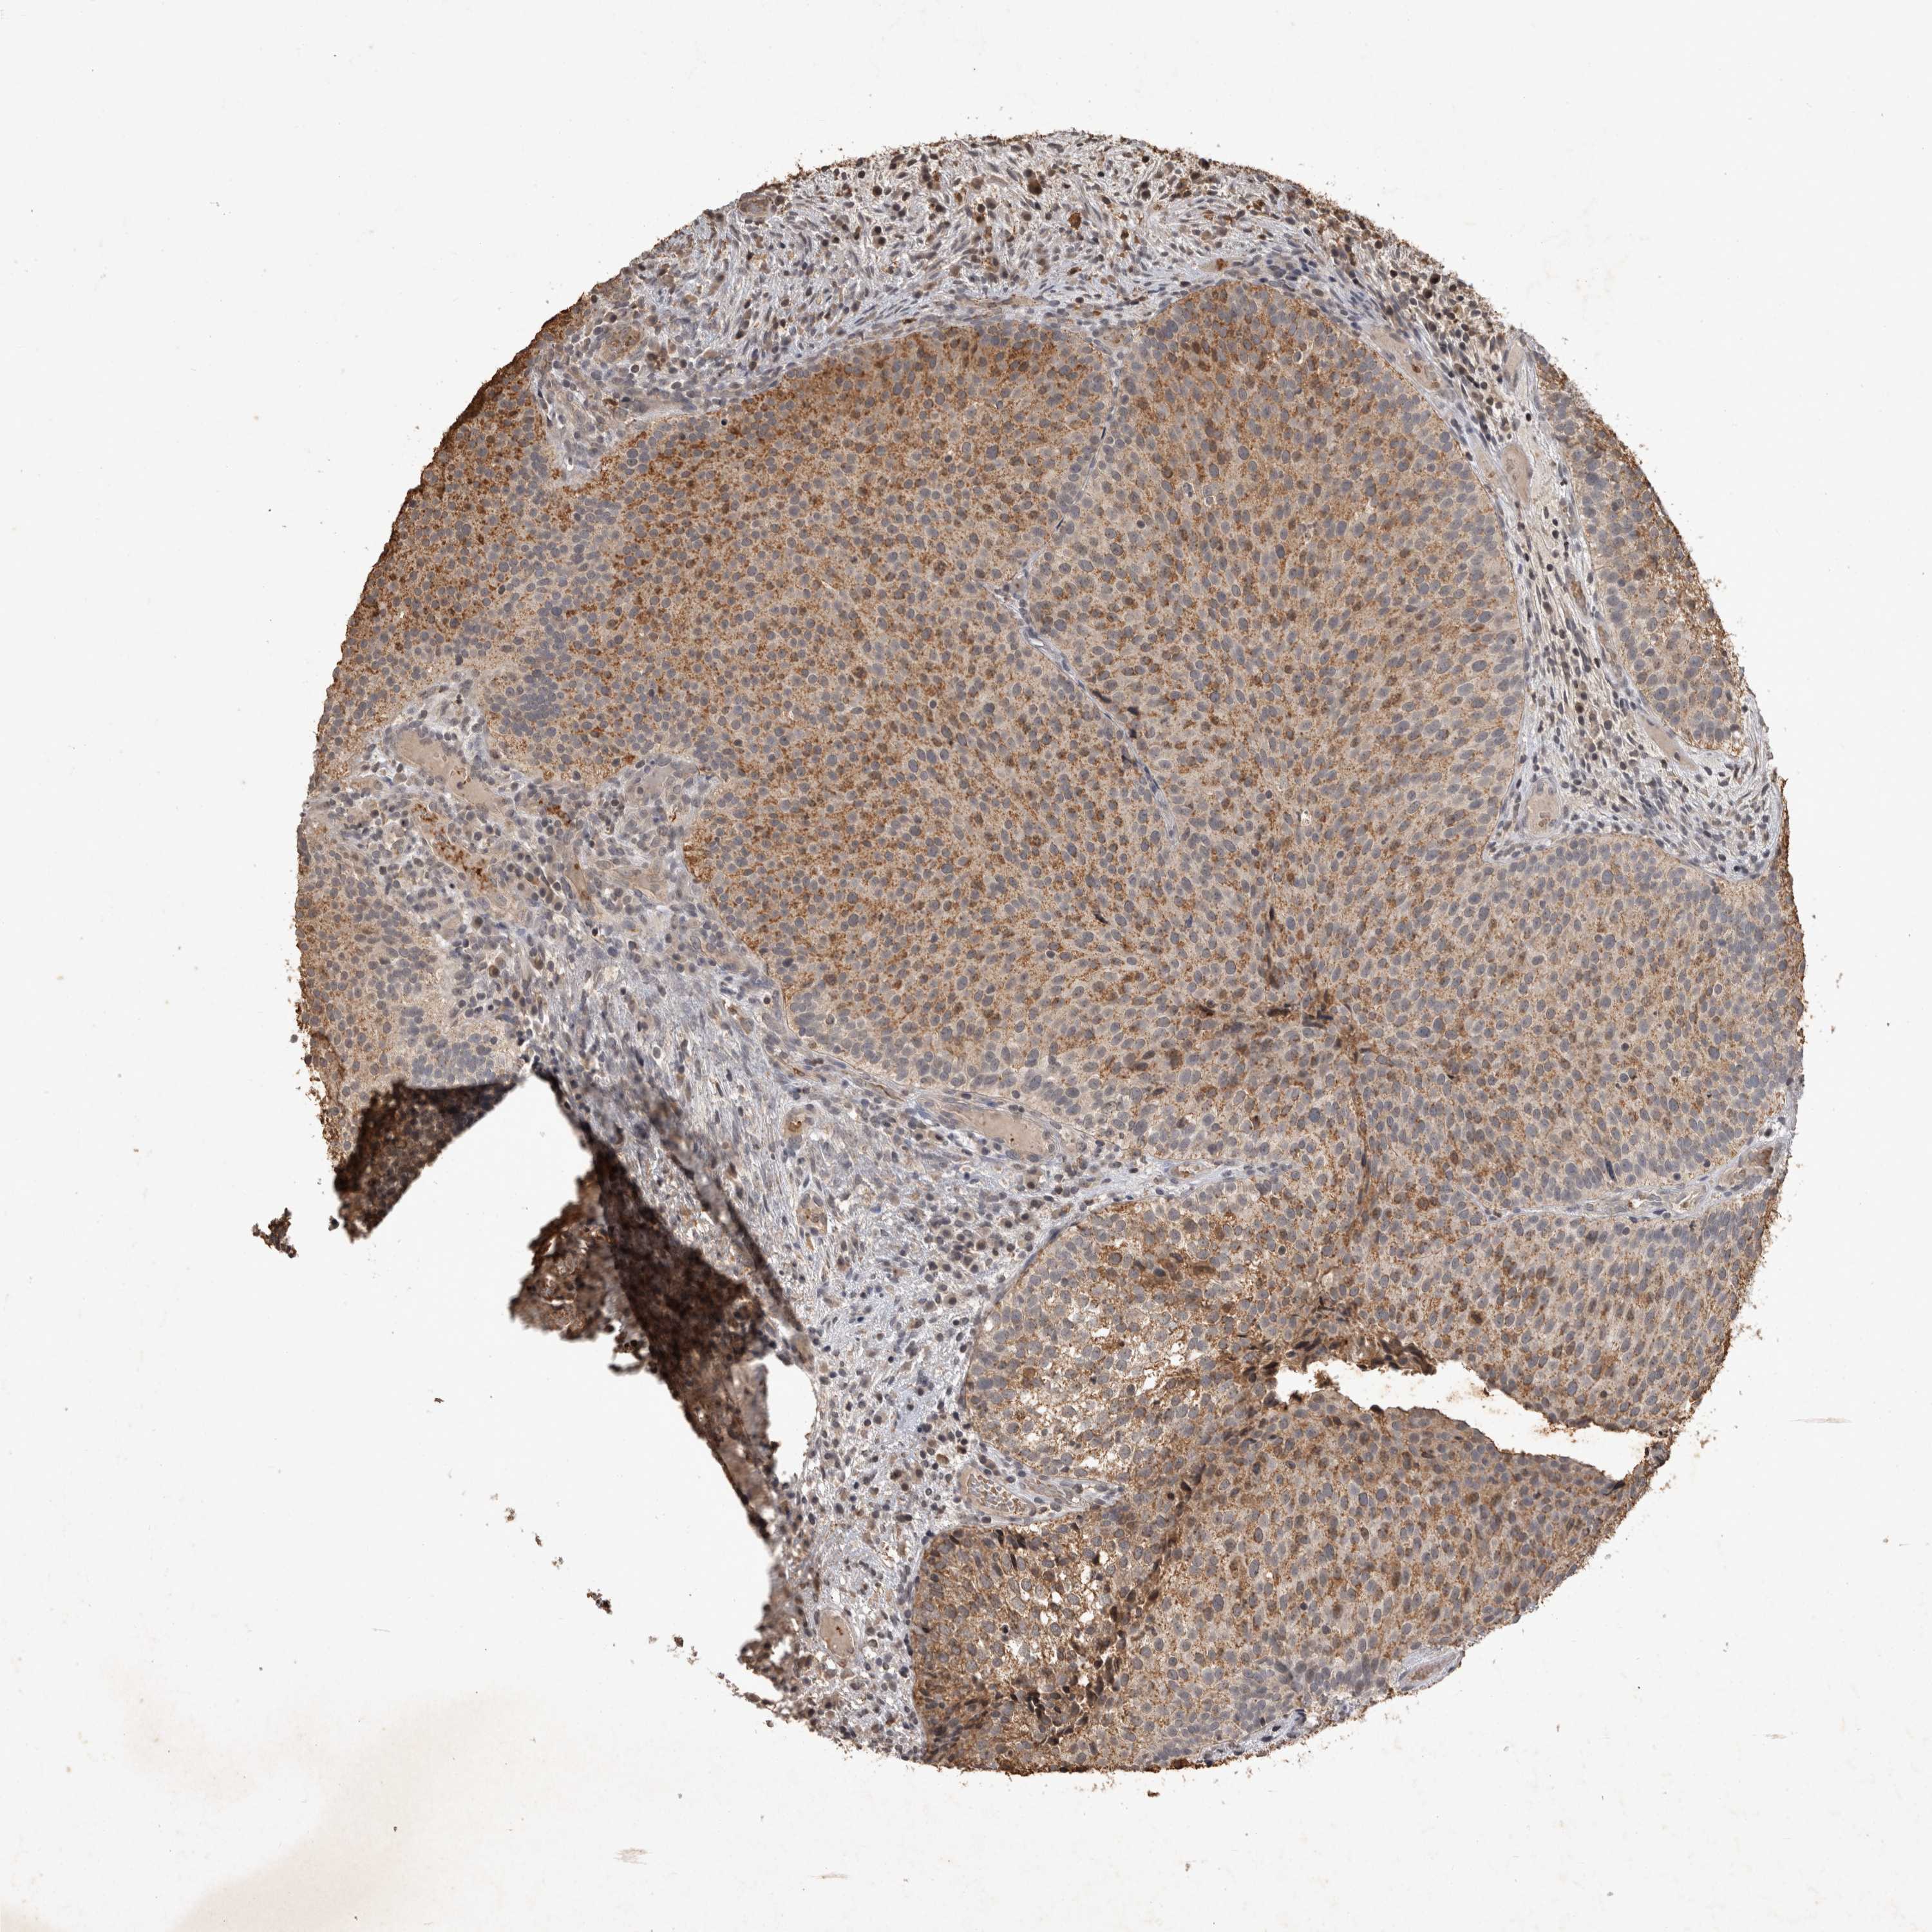

UROTHELIAL CANCER - Protein expressioni

A mouse-over function shows sample information and annotation data. Click on an image to view it in a full screen mode. Samples can be filtered based on level of antibody staining by selecting one or several of the following categories: high, medium, low and not detected. The assay and annotation is described here.

Note that samples used for immunohistochemistry by the Human Protein Atlas do not correspond to samples in the TCGA dataset.

Antibody stainingi

Antibody staining in the annotated cell types in the current human tissue is reported as not detected, low, medium, or high, based on conventional immunohistochemistry profiling in selected tissues. This score is based on the combination of the staining intensity and fraction of stained cells.

Each image is clickable and will lead to virtual microscopy that enables deeper exploration of all samples and also displays staining intensity scores, fraction scores and subcellular localization as well as patient and tissue information for each sample.

Antibody CAB025973

Staining

High

Medium

Low

Not detected

Intensity

Strong

Moderate

Weak

Negative

Quantity

>75%

75%-25%

<25%

None

Location

Nuclear

Cytoplasmic/membranous

Cytoplasmic/membranous,nuclear

Urothelial carcinoma, Low grade

Urothelial carcinoma, High grade